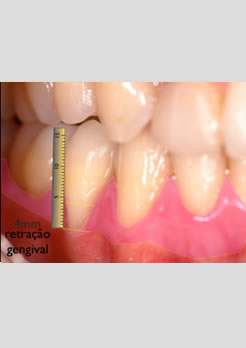

Antes – Retração gengival de 4mm com uma faixa de menos de 0,5mm de gengiva inserida na região cervical do dente e com extrema necessidade de reposição tecidual para um melhor prognóstico futuro do pré molar afetado